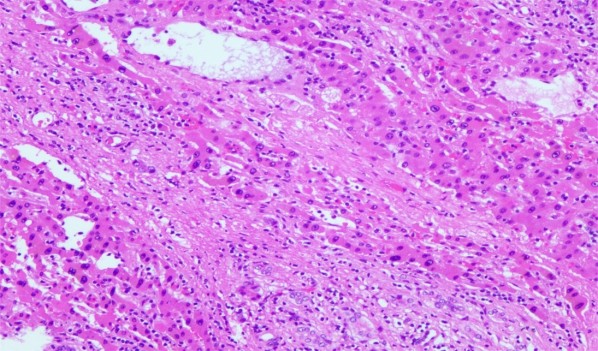

简而言之,在显微镜下,脂肪肝的主要组织学表现包括:

肝细胞脂肪变性、气球变性、小叶炎症和纤维化。此外,还可能出现其他病理学表现(如Mallory小体、巨大线粒体、糖原核、轻度的铁沉积以及局部的糖原贮积)。

(纤维化:肝细胞周围出现胶原纤维沉积,逐渐发展为肝纤维化;晚期脂肪肝可发展为肝硬化,表现为肝小叶结构破坏、假小叶形成。)